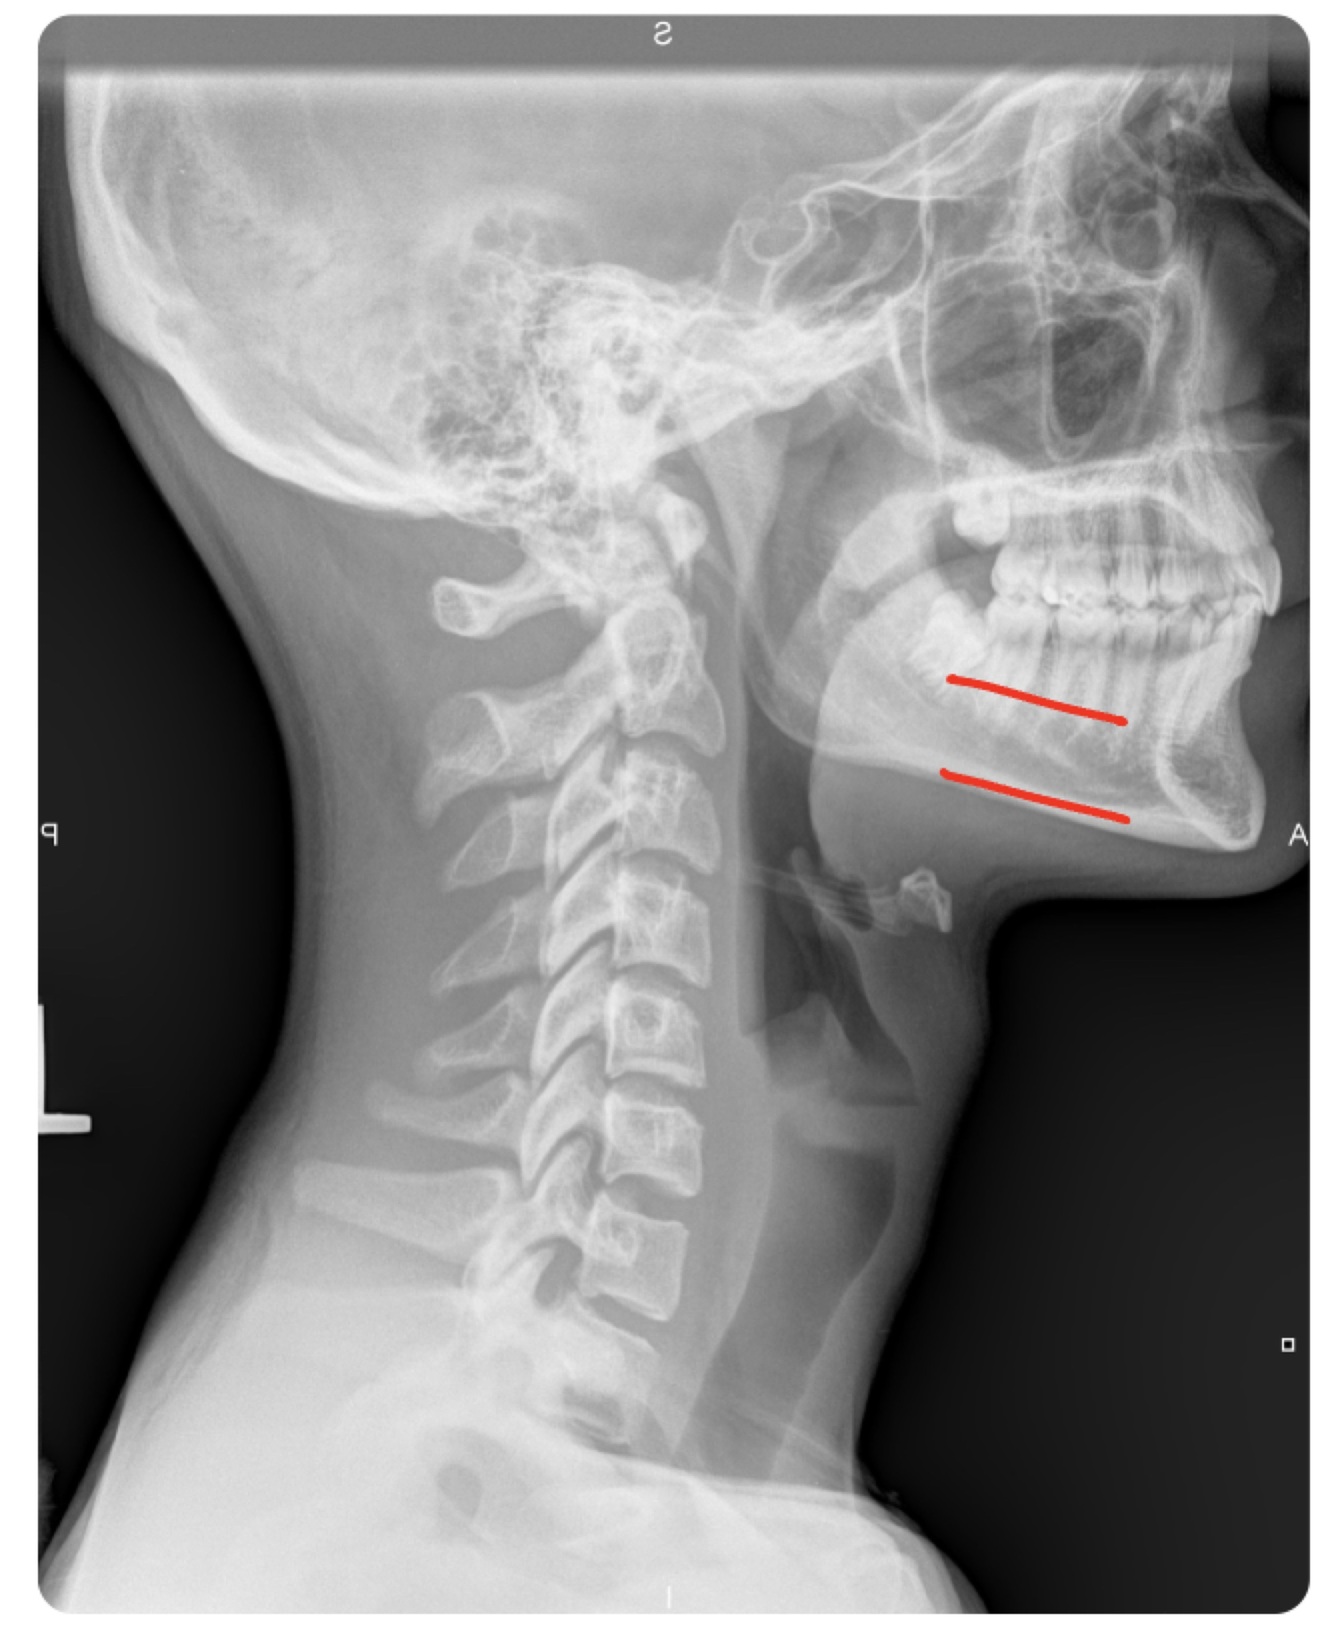

LATERAL CERVICAL LANDMARKS lateral cervical view

A

external acoustic meatus

Lateral cervical view

mastoid process (air cells)

posterior tubercle of c1

angle of mandible

EOP

Q

spinous process C2-C7

sella turcica

dens

posterior arch of C1

lamina c2-c7

vertebral body c2-c7

rami of mandible

body of mandible

anterior tubercle c1

zygapophyseal joints

petrous portion

occipital condyle

Lateral cervical

superior endplate tips

inferior endplate tips

25

disc spaces

26

atlanto-dental interspace

27

hyoid bone